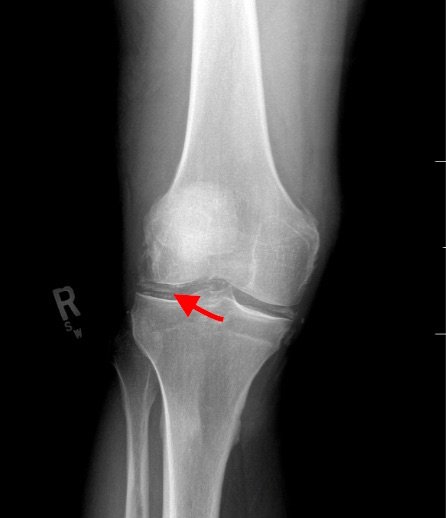

Radiographs of the knee showed multiple radio-dense lines paralleling the articular surface (see red arrows) consistent with calcium pyrophosphate crystal deposition within the joint often seen in calcium pyrophosphate disease (CPPD) also known as pseudogout.

Patients commonly present to the emergency department with non-traumatic joint pain. Arthrocentesis is an important diagnostic tool to evaluate for septic arthritis, gout, or pseudogout. Arthrocentesis can demonstrate crystals or abnormal cell count, gram stain, and culture.[1] In the evaluation of joint pain, plain films are usually obtained to evaluate for fracture, dislocation, effusion, or secondary signs of infection. In this case the classic x-ray supported the diagnosis of CPPD.2 The patient was found to have positively birefringent rhomboid shaped crystals consistent with pseudogout on arthrocentesis. Gram stain and culture were both negative. The patient was discharged with NSAIDs and had significant improvement in symptoms upon follow up with primary care physician in 3 days.